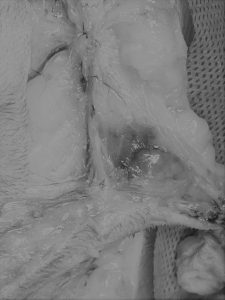

巨大な乳腺の静脈がみえます

腫瘍とおもわれるものも確認できました

こんなに範囲が広くなってしまうんですね

この症例は腹膜播種を疑うので(できるだけ切除)予後は悪いかもしれません、